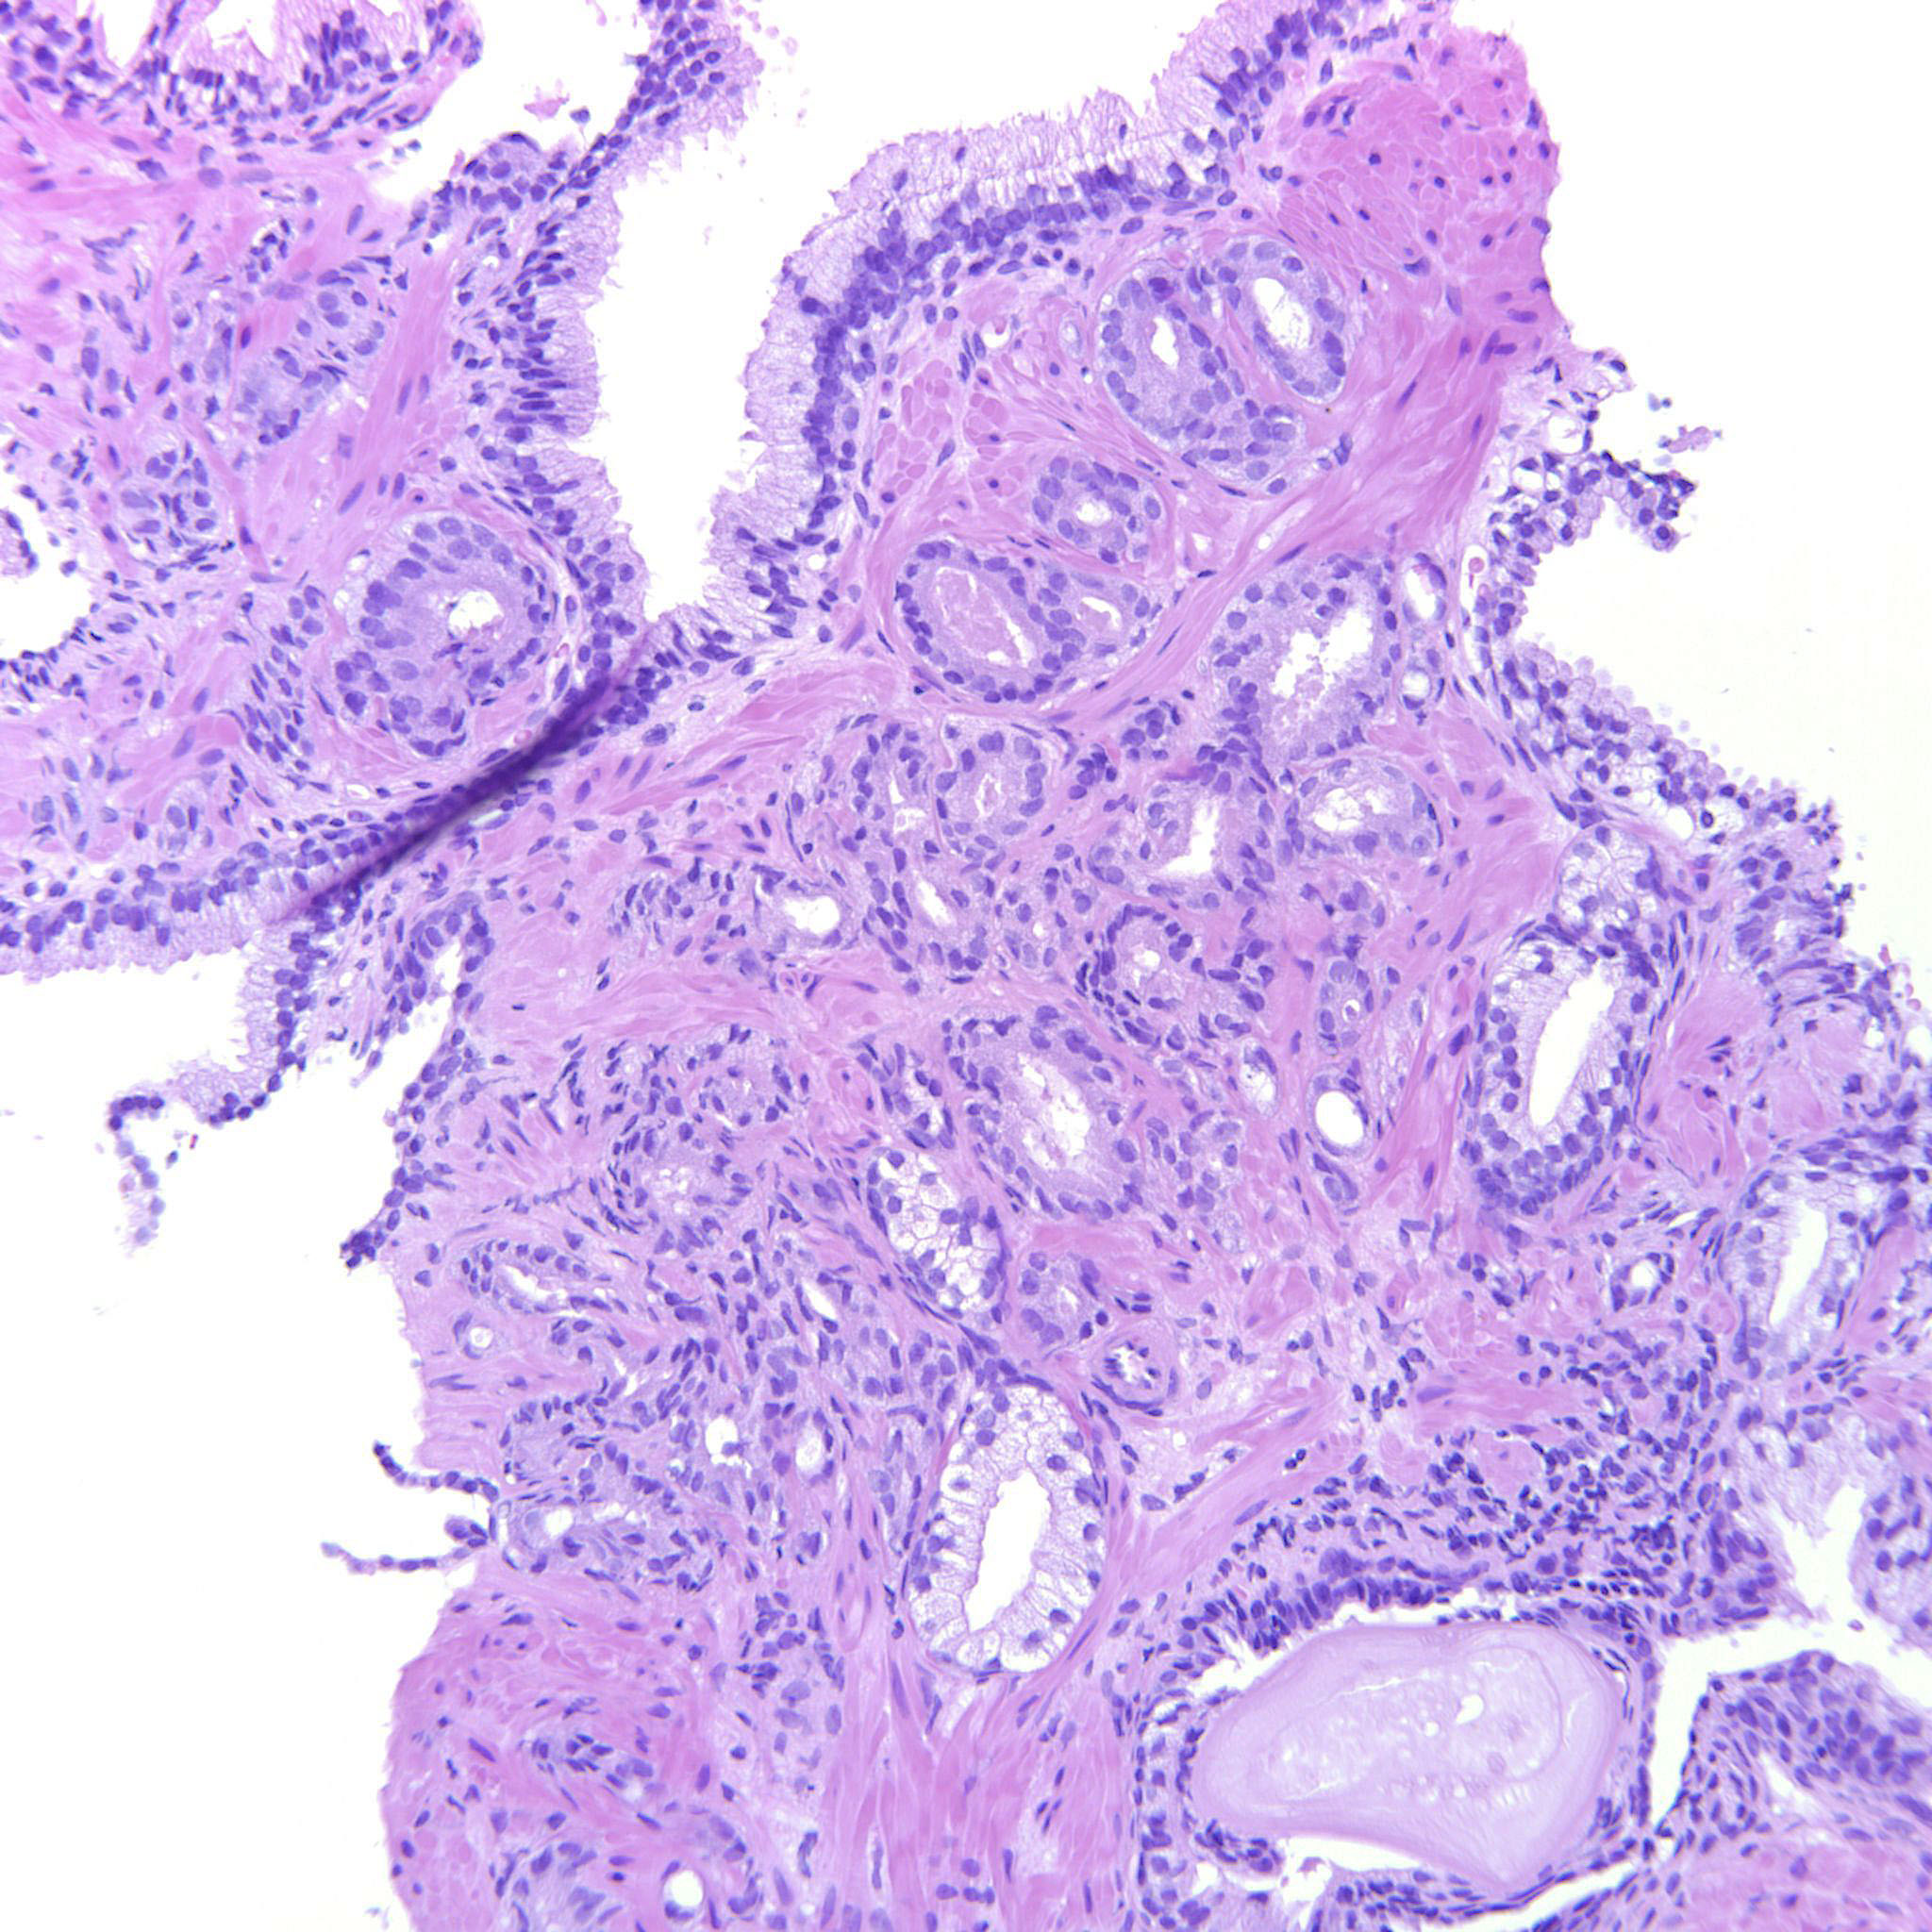

Prostate cancer grading

Case ID: 480